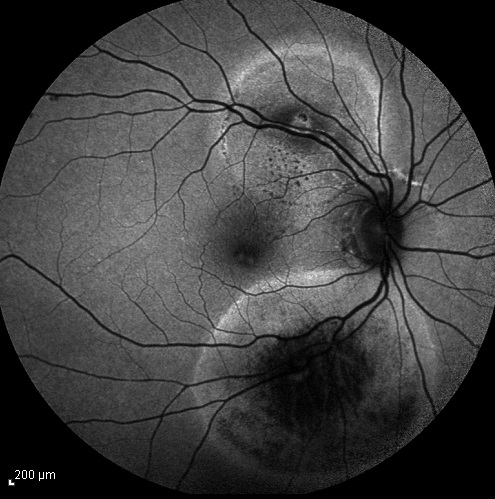

При офтальмоскопировании ишемические зоны не видны, на их существование косвенно могут указывать облитерированные сосуды, некоторая бледность и локальная отечность сетчатки. Нередко неперфузируемые области сетчатки окружены расширенными сосудами и микроаневризмами. Только флюоресцентная ангиография позволяет определить и четко локализовать ретинальные ишемические зоны. На флюоресцентных ангиограммах они выглядят в виде темных, серых, нефлюоресцирующих или гипофлюоресцирующих участков сетчатки, часто окруженных расширенными флюоресцирующими, с экстравазальным выходом контраста сосудами и микроаневризмами по краям ишемии. Ишемические зоны являются предвестниками неоваскуляризации, которая может развиваться на диске, сетчатке или радужке.

Ишемия макулы является последствием окклюзии перифовеальных капилляров. При офтальмоскопии ишемию макулы определить не представляется возможным. На ее существование иногда могут указывать облитерированные (в виде белых полосок) сосуды, расположенные в макулярной зоне. Также неперфузируемая область, как правило, ограничена несколько расширенными и извитыми сосудами и микроаневризмамй, расположенными по наружному краю ишемической зоны. Только флюоресцентная ангиография позволяет точно диагностировать ишемию макулы. При флюоресцеинангиографическом исследовании в макулярной области определяются темные нефлюоресцирующие участки, по наружным краям которых расположены расширенные флюоресцирующие, с экстрава-зальным выходом контраста, сосуды и микроаневризмы.